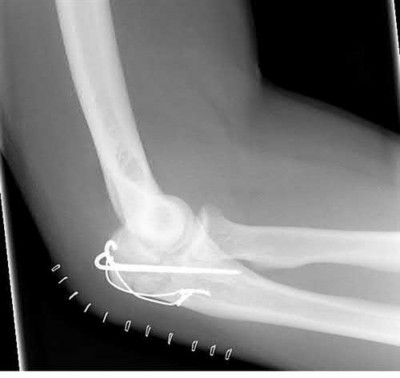

A 34-year-old male falls from a roof and sustains a right elbow dislocation that is closed reduced in the emergency room. An AP radiograph is shown in Figure A. This injury pattern is at highest risk for which of the following?

Anteromedial coronoid facet fracture and LCL injury following an elbow dislocation is commonly associated with varus posteromedial rotatory instability. Varus and posteromedial rotation force on the forearm results in rupture of the LCL from its humeral origin. As the LCL ruptures, the medial coronoid process is fractured as it impacts against and under the medial trochlea. Fracture involvement of the sublime tubercle, where the MCL attaches, can lead to more instability. Ulnar neuropathy can be seen following this injury pattern but AIN and PIN nerve palsy do not commonly characterize this injury pattern.

The review article by O'Driscoll highlights key points in diagnosis and management of capitellum, distal humerus, coronoid, and terrible triad injuries.

The article by Doornberg and Ring is a Level 4 study of 18 patients that sustained varus posteromedial rotational injuries resulting in anteromedial facet coronoid fractures. They found that lack of fixation at injury or malunion of the anteromedial facet were significant predictors of suboptimal functional outcome and development of arthrosis.

The anteromedial facet is highlighted in yellow as displayed in Illustration A. Illustration B depicts the lateral collateral ligament injury also evident during

varus stress fluroscopic examination, due to tension failure of the LCL off its humeral origin during the various mechanism.